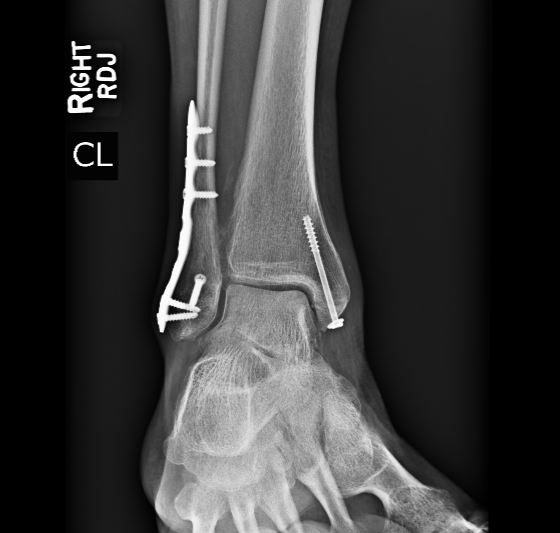

"In September of 2021 I suffered a trimalleolar fracture of my right ankle in a freak accident. That was on a Saturday, and early Monday morning I was seen by Dr. Harrod, who said that surgical intervention would be required. He operated on my ankle that Thursday, inserting two metal plates and several pins. For two months I could not put any weight on that foot, and for several weeks after that I was in a walking boot. I began regular physical therapy in January of 2022, and now, in late May, I walk several miles a day and keep up an exercise and stretching routine. I still experience some soreness and swelling in the ankle, but I look forward to spending this summer teaching in Vermont and hiking, swimming, and riding my bike."